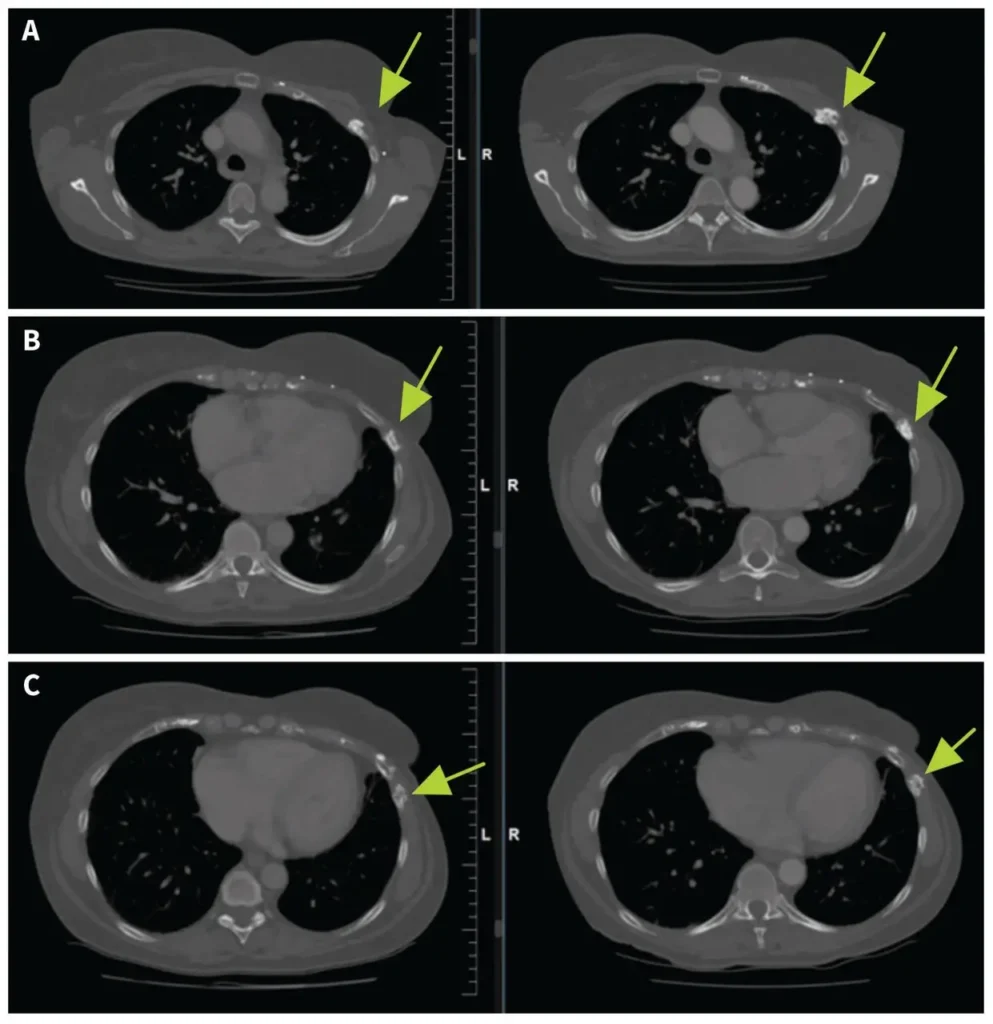

- CT scans showed healing in ribs 3 through 7 after 11 months of follow-up.

Seven years after her recurrence, the woman began experiencing left chest discomfort. Her symptoms progressed over three years. CT imaging revealed fractures in her second through seventh ribs, with sclerosis, cortical irregularity, and callous formation. A radiologist flagged concerns for radiation-induced rib fractures from osteoradionecrosis.

CT imaging performed 11 months after her baseline scan showed interval healing of ribs 3 through 7, with no new lucencies or fractures. She subsequently reduced her pentoxifylline dose to 400 mg once daily while maintaining her response.